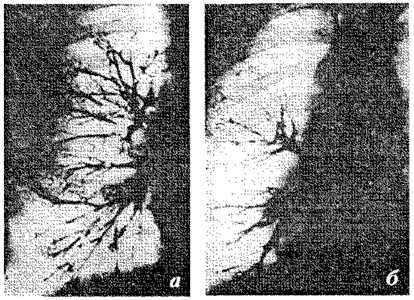

Во многих работах (Платонов, Буль, Мягер, Панов и др.) описаны изменения на физиологическом, патофизиологическом, нейрохимическом уровнях, вызываемые воздействием гипноза, аутогенной тренировки и других методов психотерапии (рис. 3).

Рис. 3. Бронхограмма больной. а — бронхограмма больной, произведенная до внушения астматического приступа; контрастное вещество заполняет все бронхиальное дерево; б — бронхограмма той же пациентки, у которой развился внушенный астматический приступ; определяется значительное сужение просвета бронхов и исчезновение контрастного вещества на периферии бронхиального дерева (по Булю).